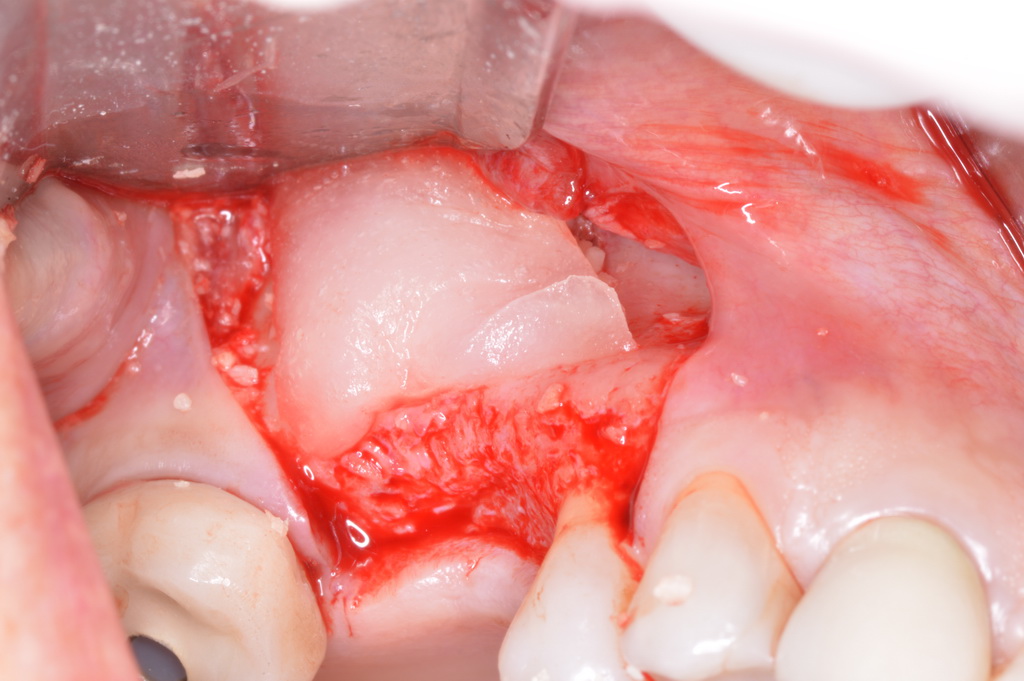

The patient had been referred for an implant consultation for the mandibular right canine. She had very deep probing depths on the lingual. When the flap was raised, a significant amount of subgingival calculus was seen as a local risk factor (Figure 18). However, she had no significant pathology to remove from the situation. Debridement was performed the same as in Case 3 with the rotary ultrasonic and manual instrumentation.

The defect was obturated with mineralized freeze-dried bone and hydrated with platelet-derived growth factor. As with any growth factor, when implementing it clinically, all growth factors require a carrier to bring that growth factor to the desired site, which do not elicit an inflammatory response. In this situation, it is the mineralized freeze-dried bone allograft. This combination was demonstrated by Rosen et al8 to be efficacious in treating intrabony defects. A biologic approach was taken both in terms of the graft and membrane (Figure 19). Primary closure was achieved.

Subgingival calculus and severe bone loss.

Figure 18